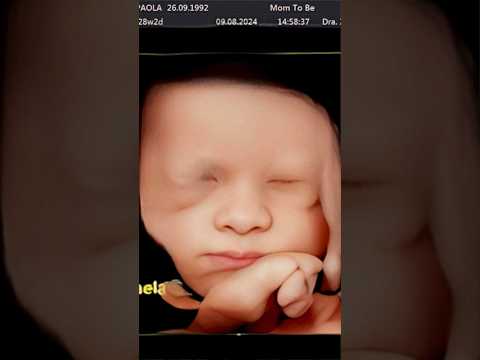

Por Fin Conocemos A Nuestros Bebés #Paopoulain #Fichis #Amoreterno ─ AMOR ETERNO